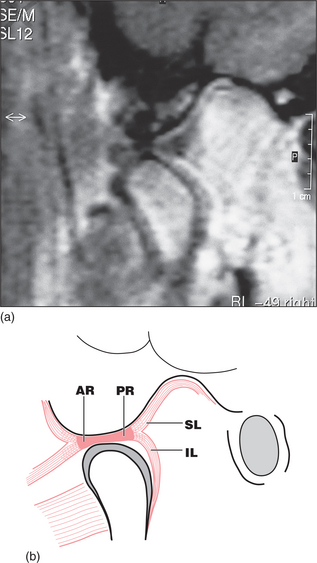

Many anatomy texts show the disc within the TMJ to be superior and slightly anterior to the condylar head when the teeth are in occlusion, with the two main ridges of the disc placed one behind and one in front of the condyle (Fig. 16.2). During mouth opening the condyle rotates against the disc and the disc slides forwards and downwards along the articular eminence, but the ridges on the disc remain on either side of the condylar head (Fig. 16.3). This forward slide in the upper joint space is called translation. In general, much of the early part of mouth opening occurs as a hinge movement in the lower joint space and later in opening a greater part of the movement is translatory.

image

Fig. 16.2 (a) MRI of the normal disc/condyle relation, mouth closed. (b) Diagram of the same. AE = articular eminence; AR = anterior ridge of disc; PR = posterior ridge of disc; GF = glenoid fossa; SL = upper lamina of posterior attachment; EAM = external auditory meatus; IL = lower lamina of posterior attachment; CH = condylar head; SPt = superior pterygoid muscle.